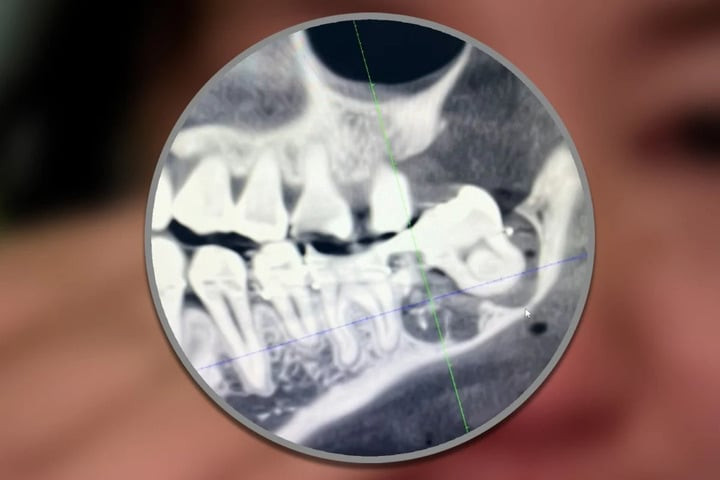

Các bác sĩ nhổ nhầm răng hàm bên cạnh chiếc răng khôn của Wu.

Răng khôn của cô Wu bị các bác sĩ Bệnh viện Thành phố An Khánh nhổ nhầm

Cô Wu, 34 tuổi, cư trú tại tỉnh An Huy, Trung Quốc, đã đến Bệnh viện Thành phố An Khánh vào ngày 12/3 để thực hiện nhổ răng khôn. Tuy nhiên, bác sĩ đã sai sót khi loại bỏ nhầm chiếc răng bên cạnh vẫn còn khỏe mạnh, sau đó cố định lại vào vị trí cũ. Khuôn mặt của cô sưng to, kéo theo những cơn đau kéo dài nhiều ngày.